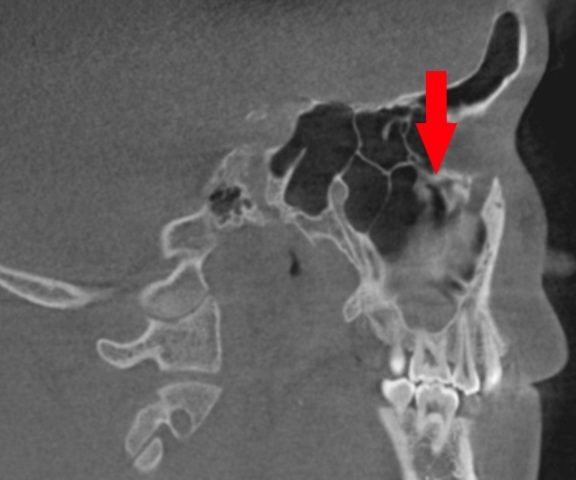

緑矢印 正常な上顎洞

黄矢印 膿がたまっている上顎洞

赤矢印 原因になった歯根

(上顎洞の底の骨が、溶けています)

頬骨 痛いとき 急性上顎洞炎の治療 根管治療 CTで根管長測定1

根管治療の前に、CTで根管長測定します。

18.6mm。

横から見た歯です。

頬骨 痛いとき 急性上顎洞炎の治療 根管治療 CTで根管長測定2

後から見た歯です。

根管長は、18.9mです。